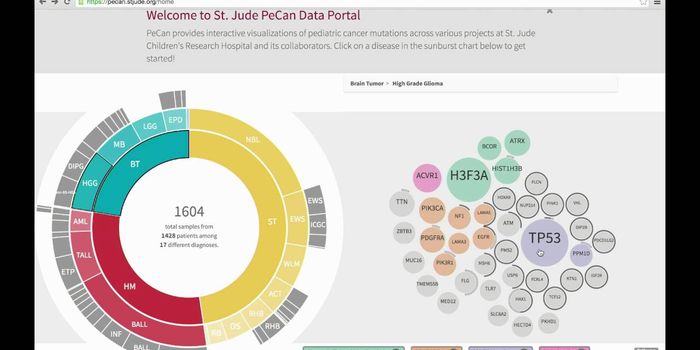

JAN 01, 2018VideosA rare form of brain cancer that strikes mostly children under the age of 10 years old seems centered in a particular ar ...

AUG 31, 2017VideosIn children, brain cancer is the number one cause of cancer-related deaths. Brain tumors are extremely aggressive and of ...